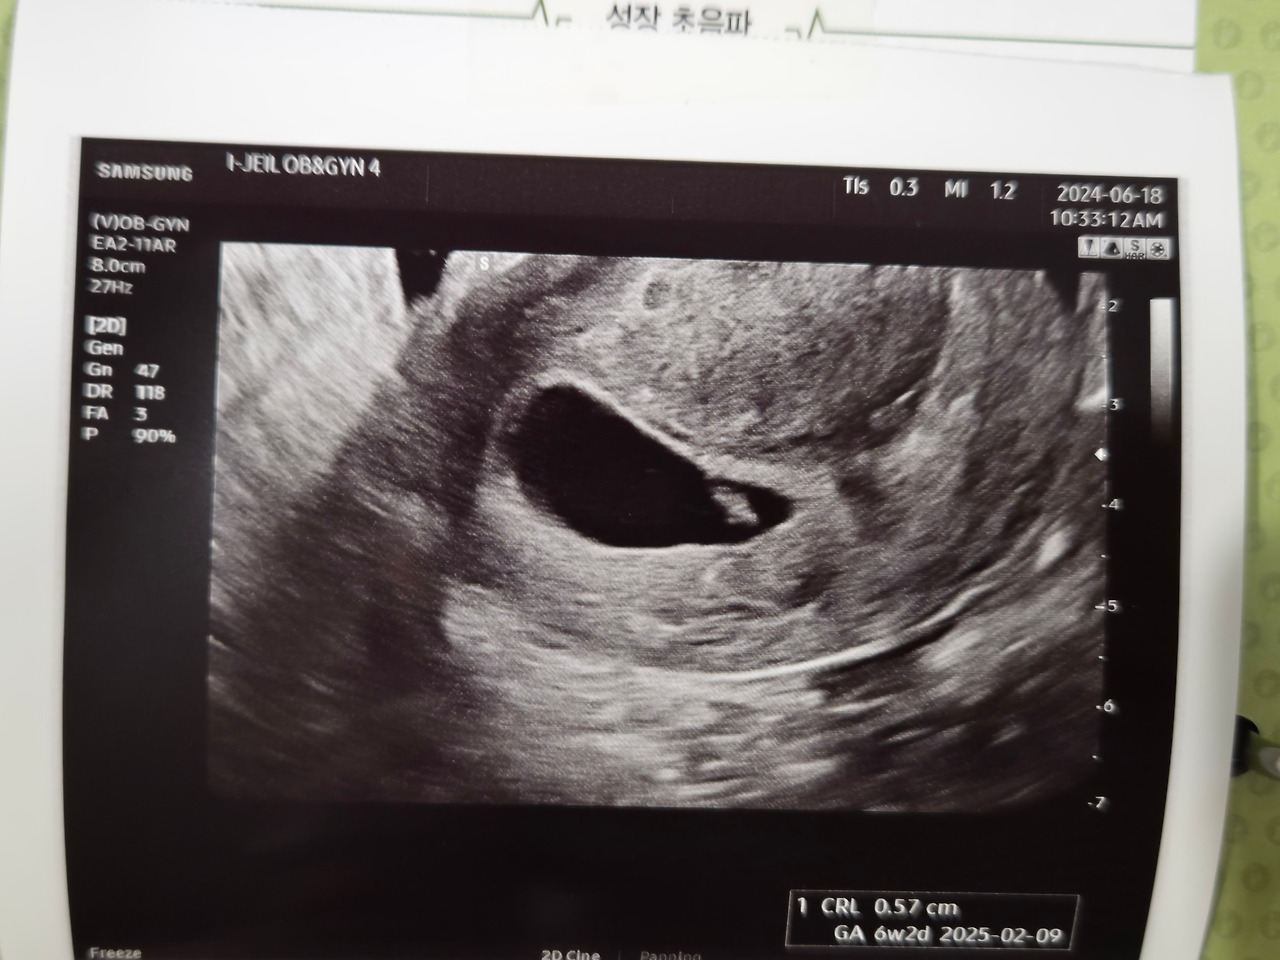

전날 임신테스트기로 미리 임신 사실을 알고 가긴 했지만, 의사 선생님께 임신 확진을 듣는 건 또 다른 느낌이었다. '내가 또 임신이라니, 그것도 6주?!' 콩닥콩닥 뛰는 아기의 심장소리를 들으며 많은 생각이 들었다. 그중 가장 먼저 떠오른 생각은 이틀 전까지 마신 술이었다. "헉! 선생님, 저 이틀 전까지 술을 마셨는데 괜찮을까요?"

선생님은 임신을 알기 전에 마신 술은 아기가 용서해 준다며 괜찮다고 하셨다. '휴, 다행이다' 싶었다. 전날 임신테스트기로 선명한 두줄을 보았을 때만 하더라도 임신을 했다는 사실 자체가 믿기지 않아 어리벙벙했었는데, 이제 보니 내 몸과 마음은 이미 우리에게 선물처럼 온 셋째를 기쁘게 받아들이고 있었다.

남편은 선생님께 제왕절개로 셋째까지 낳을 수 있는 건지, 지난 출산 때 유착이 있다고 했는데 출산하는 데 어려움이 없는 건지 등을 물어봤다. 남편은 나와 아이를 걱정하고 있었다. 내 손은 자연스럽게 배로 향했다. 따뜻했다. 9개월 만에 내 몸에 또 두 개의 심장이 뛰고 있었다. 우리에게 온 이 아이를 잘 지켜야겠다는 생각뿐이었다.